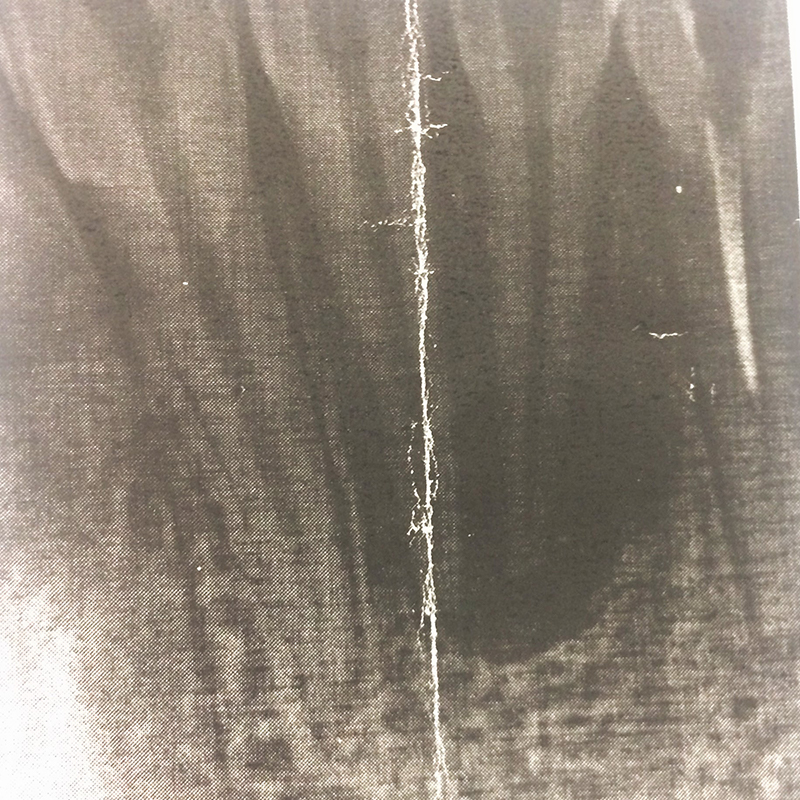

Пациент обратился в «Стоматологию Комфорта» с жалобой на острую боль в области нижних резцов, возникшую после начала лечения в другой клинике. В ходе осмотра и по результатам диагностики врач стоматолог-терапевт Вахлюева Елена Сергеевна поставила диагноз — периодонтит в стадии обострения.

В процессе лечения проведены следующие манипуляции:

- эндодонтическое лечение зубов 3.1, 3.2, 4.1, 4.2;

- пломбировка корневых каналов;

- временное восстановление коронковой части зубов.